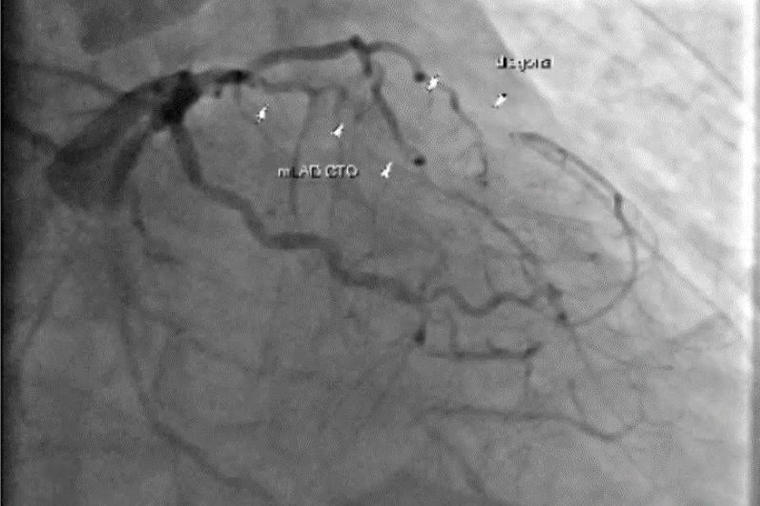

楊凱文說,個案長期以來都有冠狀動脈狹窄的問題,曾接受過支架放置手術,理論上應持續服用抗血小板藥物,但卻因自行停藥許久,導致心臟血管隨時間慢慢阻塞,進而造成心肌缺血壞死與心臟衰竭。對於心臟嚴重衰竭的病人而言,移植是唯一的救命方式。特別是個案在3條冠狀動脈全部阻塞,左心室有巨大血栓,且心臟肌肉大範圍壞死的情況下,病情相當危急。手術團隊先進行冠狀動脈繞道手術與血栓清除,並以人工補片重建心臟壁,在手術中還同步放置暫時性左心室輔助器(LVAD),協助心臟輸出血流。